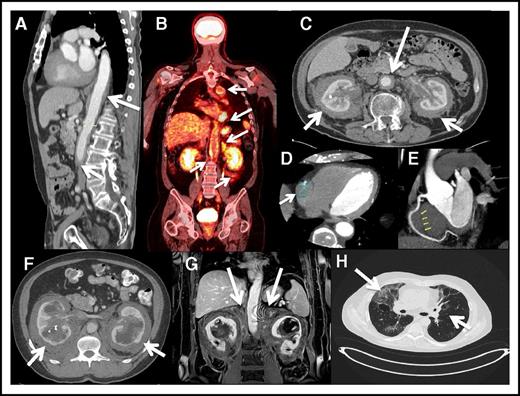

Coated aorta or circumferential encasement of the aorta (Figure 2A-C) was apparent in 62% of patients. The most common cardiac manifestation was pseudotumor of the right atrioventricular groove, apparent on cardiac CT (Figure 2D-E) in 37% of patients. Rarely involved vessels included the portocaval system, causing portal hypertension in 1 case and mesenteric vessel disease producing bowel ischemia in 3 cases. Stents were used to bypass the stenosis. A total of 5 patients had pericardial involvement; 2 had cardiac tamponade, and 4 needed pacemakers for abnormal rhythms. None of the cases had evidence of valvular disease or cardiac failure.

Cardiovascular, retroperitoneal, and lung images of ECD patients. (A) Sagittal reconstruction postcontrast CT demonstrates encasement of the thoracic aorta down to the bifurcation. (B) Coronal FDG PET-CT scan showing increased FDG uptake in the thoracic and abdominal aorta. Symmetrically encased kidneys “hairy kidney” showing increased FDG uptake. (C) Axial CT with contrast demonstrates mass-like enhancement encasing the kidneys symmetrically (“hairy kidney”). In addition, there is circumferential encasement and narrowing of the abdominal aorta (arrow). (D) Cardiac CT showing partial encasement of the right coronary artery. (E) Cardiac CT showing partial encasement of the right coronary artery. (F) Axial postcontrast CT image of the upper abdomen demonstrating mass-like perinephric stranding surrounding the kidneys with bilateral hydronephrosis. Hyperdense material within the right collecting system is a ureteral stent. (G) Postcontrast coronal MRI image of the kidneys demonstrating extension of the perinephric mass into the adrenal bed and encasement of the adrenals (arrows). (H) High-resolution CT of the chest showing interstitial fibrosis.

Retroperitoneal involvement

One-third of patients had a history of renal impairment prior to their NIH visit. A total of 65% of patients (39 out of 60) exhibited encasement of the kidneys and involvement of the retroperitoneal space (Figure 2F-G), causing renal artery stenosis in 54% of cases (21 out of 39) and ureteropelvic junction obstruction in 51% of that group of patients (20 out of 39); 13 cases were affected by both renal artery stenosis and ureteropelvic junction obstruction. Hypertension controlled by renal artery stents was reported in 4 cases and hydronephrosis needing ureteral stents in 6. Three patients had a history of requiring nephrostomy tubes. In these cases, renal function was impaired, but neither renal transplantation nor dialysis was under consideration.

Other endocrine abnormalities included hypogonadism in 60% of patients. Of the 15 females in the study, 6 had a history of amenorrhea or infertility, and 30 of the 45 males had hypogonadism confirmed by decreased total or free testosterone levels. Follicle stimulating hormone and luteinizing hormone were increased in nearly half of the patients. Insulin-like growth factor levels were abnormal (high or low) in one-third of the cases, 22% of patients had hypothyroidism, and 7% had adrenal insufficiency. Adrenal gland involvement was present in 21 cases (35%) (Figure 2G). Occasional abnormalities in parathyroid, growth, adrenocorticotropic, and prolactin hormones were seen.

Patients were generally asymptomatic from pulmonary disease, but some experienced dyspnea with exertion. Interstitial fibrosis with reticular pattern was apparent on high-resolution chest CT (Figure 2H) in 52% of patients; plain films of the chest did not reveal lung disease. Pulmonary function tests showed a restrictive pattern in 30% and an obstructive pattern in 7% of patients. The mean diffusing capacity of the lungs for carbon monoxide level was 23.0 mL/mm Hg per minute, with a range of 8.5 to 36.